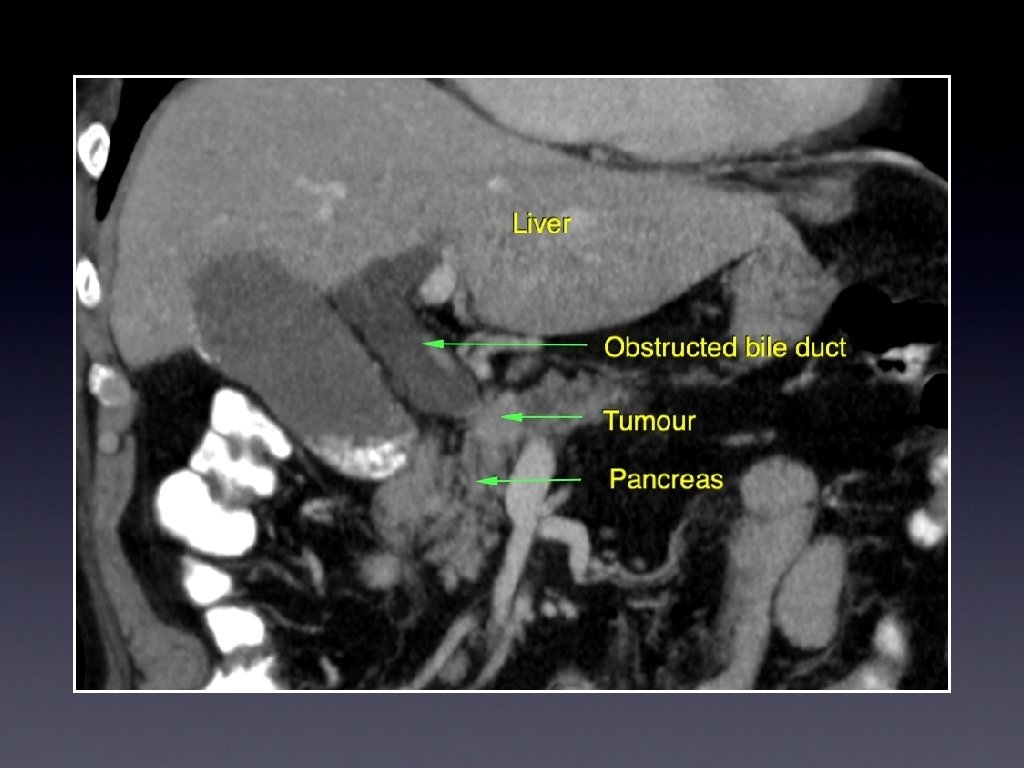

Biliary intervention; patients/ pathology • Biliary obstruction; carcinoma pancreas, cholangiocarcinoma, Lymph nodes/ adjacent tumours, hepatic metastases, benign causes. • Elderly, chronic ill-health, near end of life

Presentation • Painless jaundice • Obstructive; pale stool, dark urine • Weight loss • Abdominal or back pain • Other indicators of primary or secondary disease

Investigations • Ultrasound • CT for evaluation, and full staging • Magnetic resonance cholangiography (MRCP)